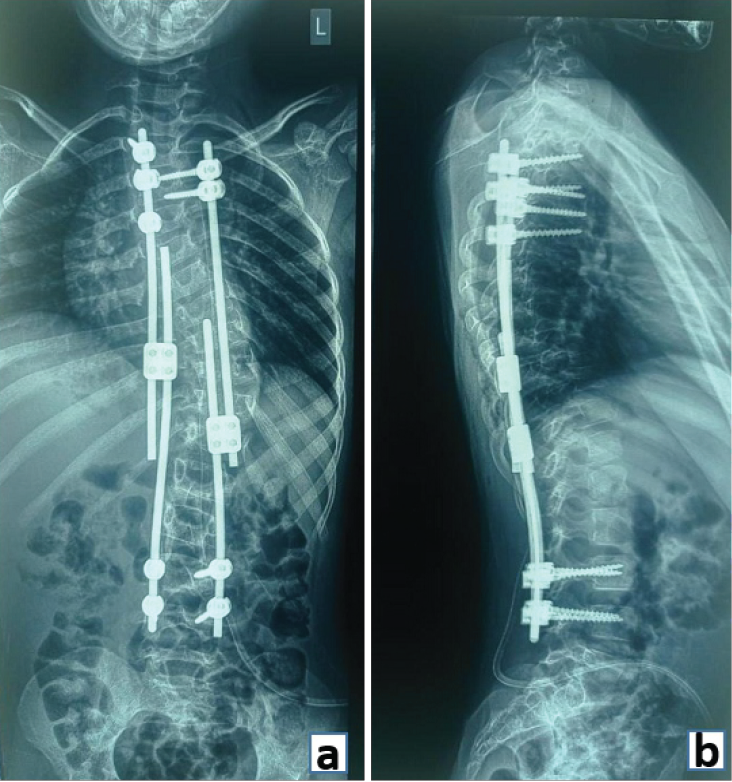

Similarly, growth rod constructs used in the treatment of early onset scoliosis are another illustration of spinal stabilization (Fig. 5). Growth rods provide a means to prolong final fusion and achieve control over the progression of deformity. Periodic distraction of growth rods is done to ensure adequate growth of the spinal column and correction of the deformity. This follows a final fusion procedure once spinal growth is complete [7].

Figure 5: (a) Anteroposterior and (b) Lateral radiograph demonstrating stabilization with pedicle screws and growth rods in a case of early onset scoliosis.